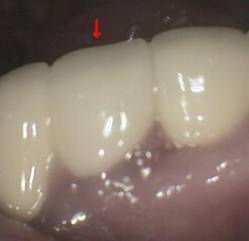

美容歯科(クイック矯正)ブリッジ

おそらく叢生(歯が重なって生えている)があったと考えられます。右下 2 番(側切歯)は抜歯されています。また支えとなっている歯 4 本のうち 3 本は神経を取っています。歯の角度を変えるためには大きく削りますがそのために神経を取る必要があったのかもしれません。抜歯された部分は歯を配列するスペース確保のためでしょうか。 写真の赤↓のある部分が抜歯された部分でダミーが入っています。このダミー部が清掃性不良でダミーの下は腫れた歯肉で塞いでいます。少しさわるだけで出血があります。